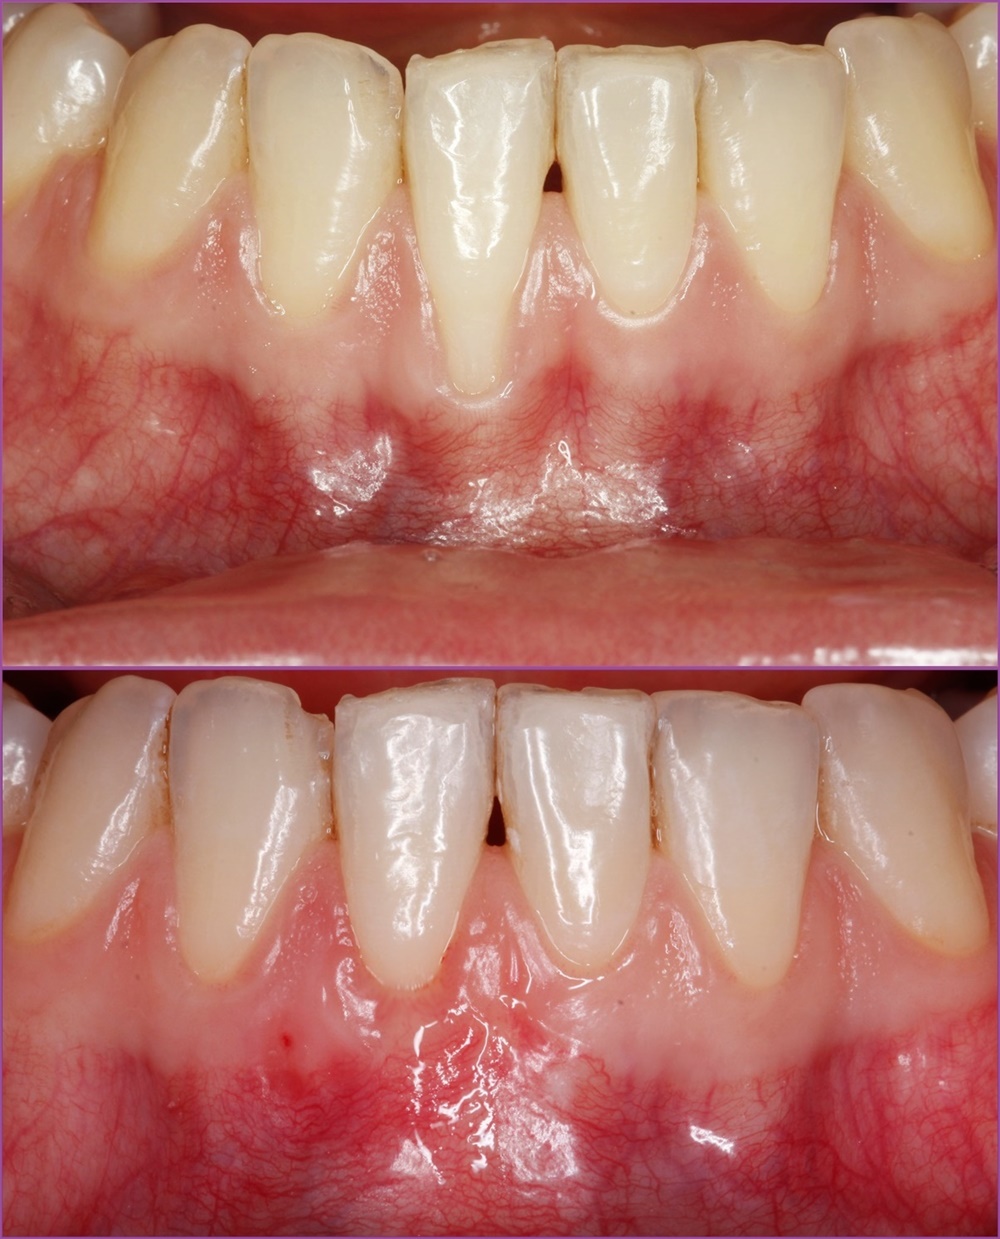

Ínyrecesszió kezelése kötőszövet-átültetéssel

A fiatal hölgy azzal a panasszal érkezett dr. Orbán Kristóf parodontológuhoz, hogy a jobb alsó első metszőfogáról az íny visszahúzódott, a fog fogmosásnál, valamint hidegre-melegre érzékeny. Szájvizsgálat és radiológiai vizsgálat alapján a diagnózisa jobb alsó első kismetsző fognál Miller III. osztályba tartozó ínyrecesszió.

Így hát nem csoda, hogy sikerült az ínyt közel tökéletes pozícióba visszaépíteni és a fognyaki érzékenység is nagymértékben javult. A hölgy rendkívül elégedett volt az elért eredménnyel.